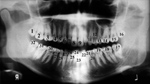

Tooth nomenclature and numbering are important for properly describing dental and mandibular lesions. Tooth nomenclature is based on tooth location and anatomic features (figure: tooth nomenclature). Central teeth refer to the two upper and two lower teeth in the most mesial, or medial, position of the mouth. Lateral teeth are the teeth directly lateral to the centrals. The centrals and laterals are also collectively referred to as the incisors. Cuspid teeth, or canines, are just lateral and posterior to the laterals and have only one cuspal or point. Bicuspids, or premolars, are located posterior to the cuspids and have two cuspals (points). Molars are posterior to the bicuspids and usually contain four cusps. The deciduous arch has four molars and no bicuspids. The permanent arch contains four bicuspids and six molars (figure: tooth nomenclature).

Tooth nomenclature |

WT-wisdom tooth (3rd molar); 2M-second molar; 1M-first molar; 2B- second bicuspid (premolar); 1B-first bicuspid (premolar); K9-canine; LI-lateral incisor; CI-central incisor. The * marks the mandibular canal.